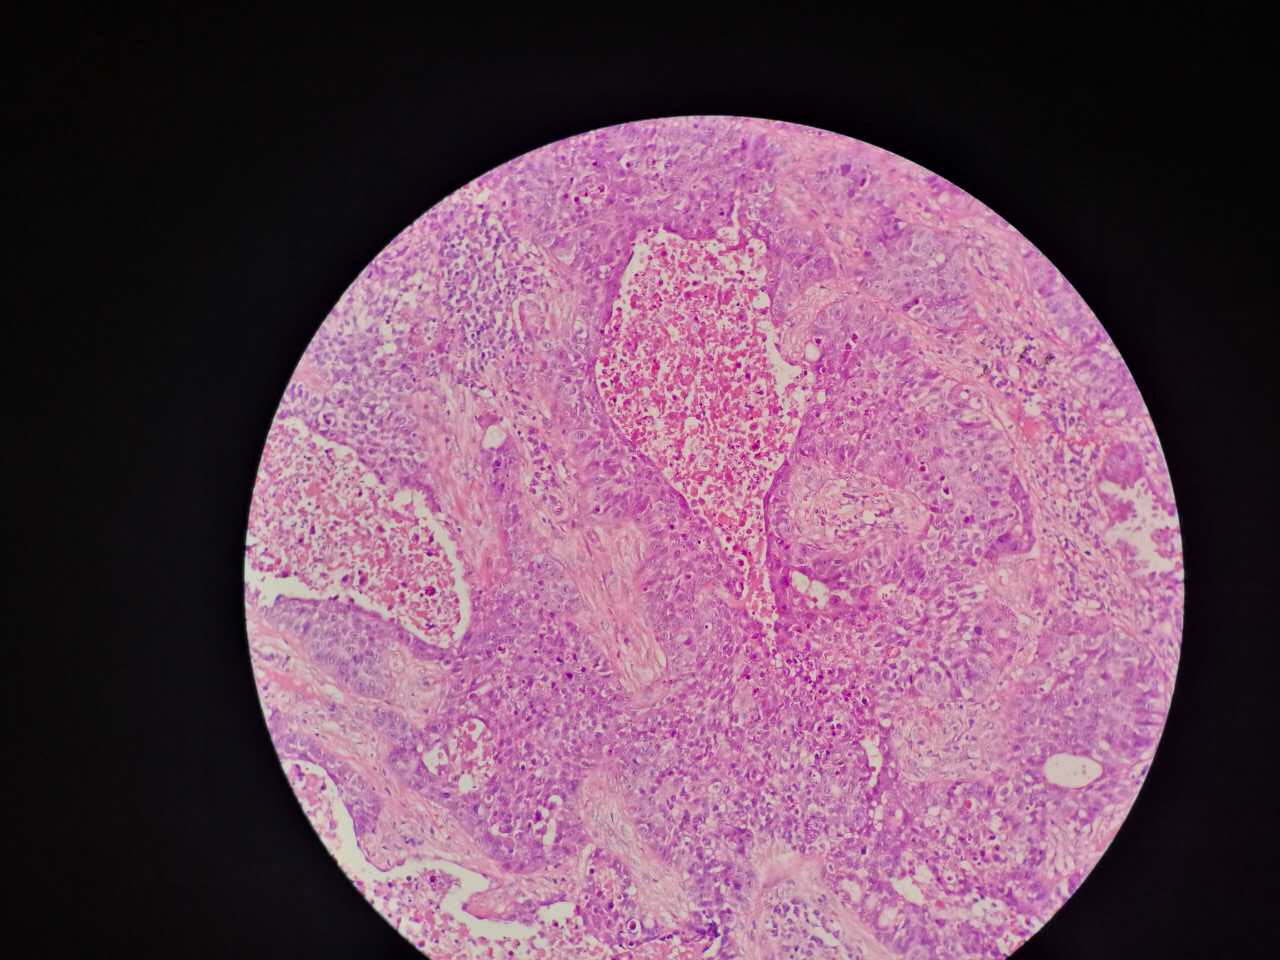

鳞癌生长,呈巢团状

巢团边界大多清楚

巢团可以很大,中央血供不足,就会坏死

坏死也可以很大

较大的粉红区都是坏死,可以看出坏死是因为巢团大,中央坏死

坏死会有许多团,有些只有一毫米大小,所以,建议增强扫描时候保留肿瘤区的薄层,以看到更多坏死区

非角化型鳞癌

细胞胖胖的,核大而淡染

也是巢团状,也容易坏死

与实体型腺癌有时难区分,做免疫组化鉴别

左边坏死挺多

红染的,核没了

特征不明显

这是一般的鳞癌,坏死大